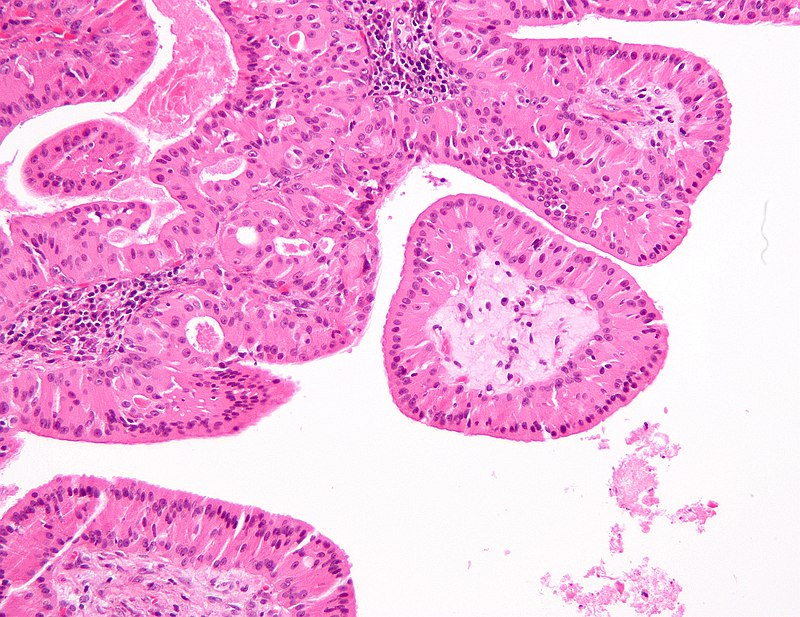

Pleomorphic Adenoma

Pleomorphic adenoma is a benign tumor made up of both epithelial and stromal tissue.

Pleomorphic adenoma is the most common salivary gland tumor.

Pleomorphic adenoma appears as a moving, painless mass that is constrained to the angle of the jaw.

Histologically pleomorphic adenomas have a myxoid component and a stromal component.

Pleomorphic adenoma is associated with the PLAG1 gene mutation.

Treatment of pleomorphic adenoma is surgical resection.

Small islands of tumor that extend through the tumor capsule frequently result in an incomplete resection.

There is a high recurrence rate for excised pleomorphic adenomas.

Rarely the benign pleomorphic adenomas may develop into their malignant counterparts carcinoma-ex pleomorphic.